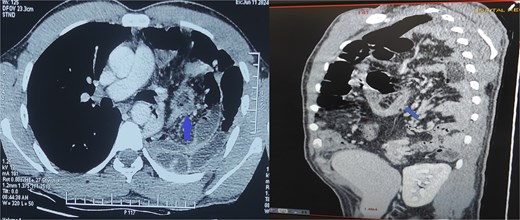

The differential diagnoses initially included pneumonia, pleural effusion, pericarditis, and hydropneumothorax. Electrocardiogram was normal. Chest X-ray revealed air-filled bowel loops in the left hemithorax (Fig. 1). A contrast-enhanced computed tomography (CT) scan of the chest and abdomen confirmed a left-sided posterolateral diaphragmatic defect with herniation of omentum, small bowel loops, appendix, caecum, ascending colon, and transverse colon into the thoracic cavity. The appendix appeared thickened with surrounding fat stranding, suggesting acute appendicitis. There was also left-sided reactive pleural effusion (Fig. 2).

Contrast-enhanced CT of the chest and abdomen showing a left posterolateral diaphragmatic hernia with herniation of bowel and omentum into the thorax. The thickened appendix with surrounding fat stranding indicates acute appendicitis.